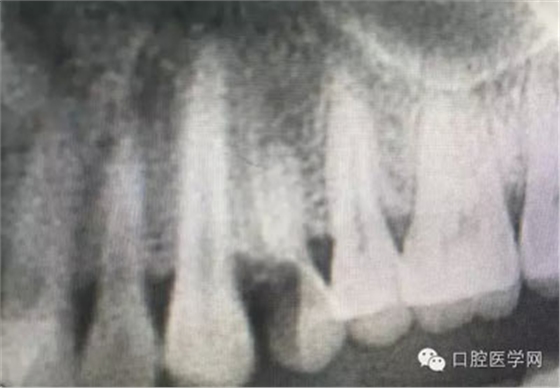

根管再治療是我們比較頭疼的,尤其是那些冠修復(fù)過(guò)的,我們有很多的麻煩需要去溝通,比如可能導(dǎo)致的側(cè)穿、可能沒有看到的腐質(zhì)、可能導(dǎo)致的崩瓷,或者是后期可能出現(xiàn)冠折......這些需要我們和患者好好的溝通。全瓷冠還好些,金屬冠根測(cè)的時(shí)候很是麻煩,總之我們做修復(fù)的時(shí)候不要單純的追求速度,追求效益,適當(dāng)?shù)淖⒁庀挛覀兊幕A(chǔ)治療和設(shè)計(jì)。